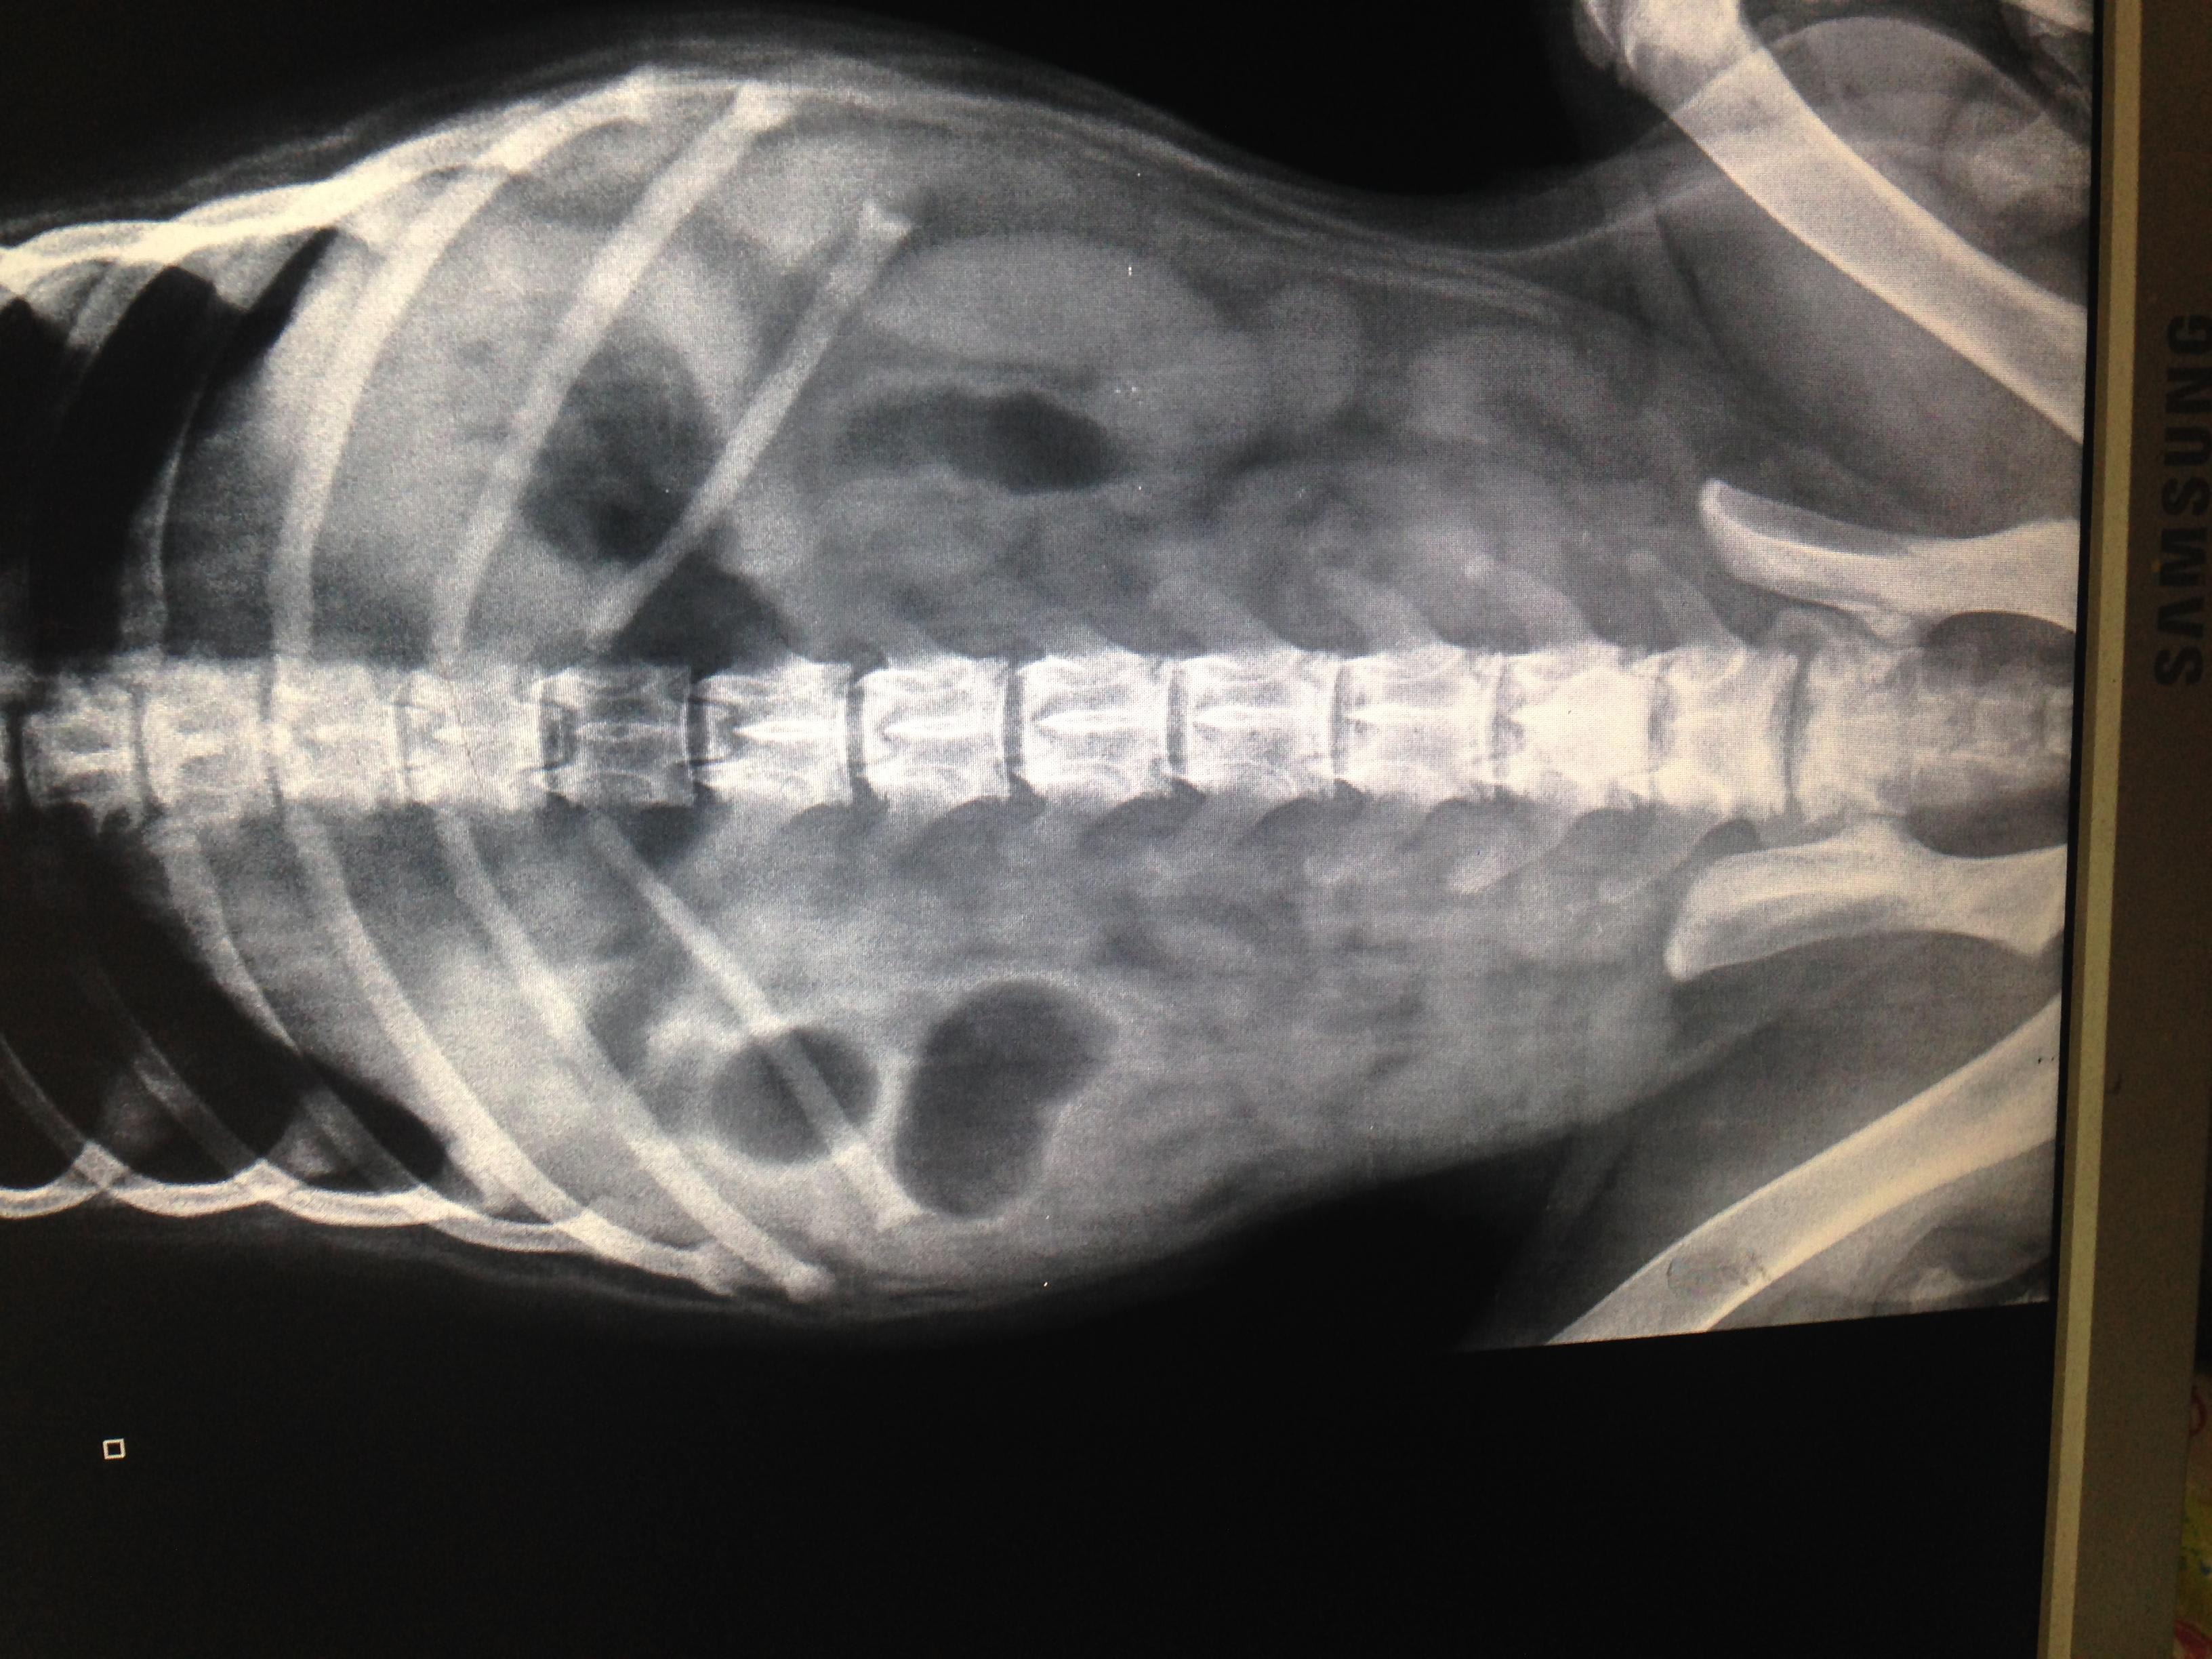

Common causes of bloody vomiting or diarrhea in a puppy include dietary intolerance, dietary indiscretion, intestinal parasites, GI blockage, toxic exposure, gastroenteritis, bacterial or viral (like parvo or distemper) infection, among others. The x-rays you provided are not diagnostic for any specific disease, but there are a couple large pockets of gas that could indicated GI blockage or a decrease in movement of the intestines, called ileus, Other diagnostics that can be performed are CBC, chemistry, parvo test, intestinal parasite screen, or coagulation profile. If you have additional diagnostic results, you can choose a one-on-one consult and we can discuss them fully and help you decide what else can be discussed with your vet.